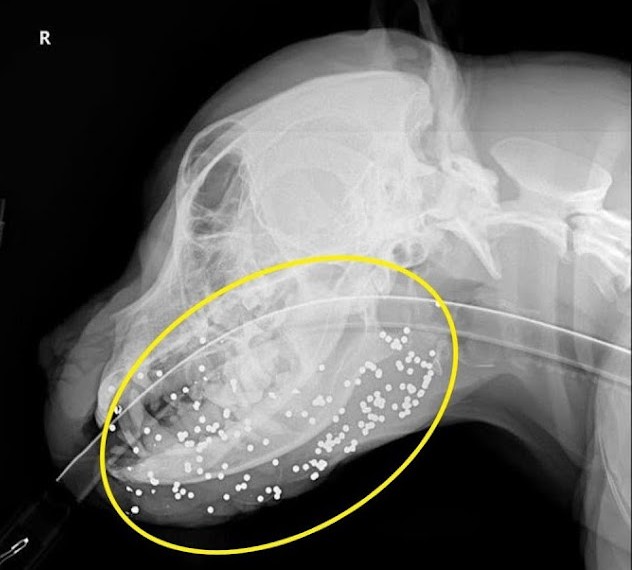

Despite having been shot multiple times with a shotgun, leaving him with over 200 pellets embedded in his body, Buck’s gentle spirit shines through.

Following the incident, Buck was taken to Vergi 24/7 for a thorough examination. The veterinary team conducted x-rays reviewed by a radiologist and promptly started him on IV fluids, antibiotics, and pain relief medication.

Most of the pellets are lodged in Buck’s face, but fortunately, the vet does not anticipate the need for extensive reconstructive surgery. Some minor procedures could help align the tissues more effectively.

Initially, there was a concern that Buck might be lame due to a possible pellet in his joint. The plan was to monitor his condition over two weeks.